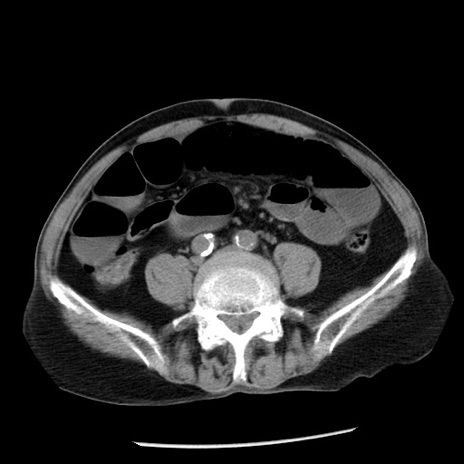

症例26(横断像)

【症例】80歳代男性

【主訴】嘔吐

【現病歴】昨晩2回嘔吐あり、今朝になっても嘔吐あり。来院。

【既往歴】胃潰瘍

【身体所見】意識清明、BT 37.6℃、BP 166/95mmHg、HR 100bpm、SpO2 97%、腹部:平坦・軟、腸蠕動音聴取良好、圧痛なし。

【データ】WBC 21900、CRP 1.46